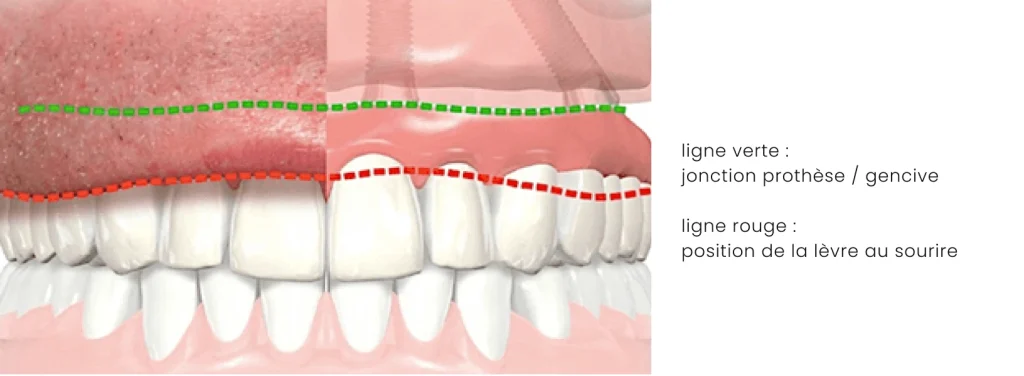

Fausse gencive

La présence et le volume de fausse gencive sur votre prothèse dépendent de la quantité de perte osseuse verticale de votre mâchoire.

Pour compenser la perte osseuse verticale, une greffe osseuse peut être proposée mais impose plusieurs interventions, une durée allongée et un coût supplémentaire.

Le rajout de fausse gencive sur la prothèse est une alternative simple et esthétique. La jonction prothèse/gencive doit être plus haute que la lèvre au sourire pour ne pas être visible.